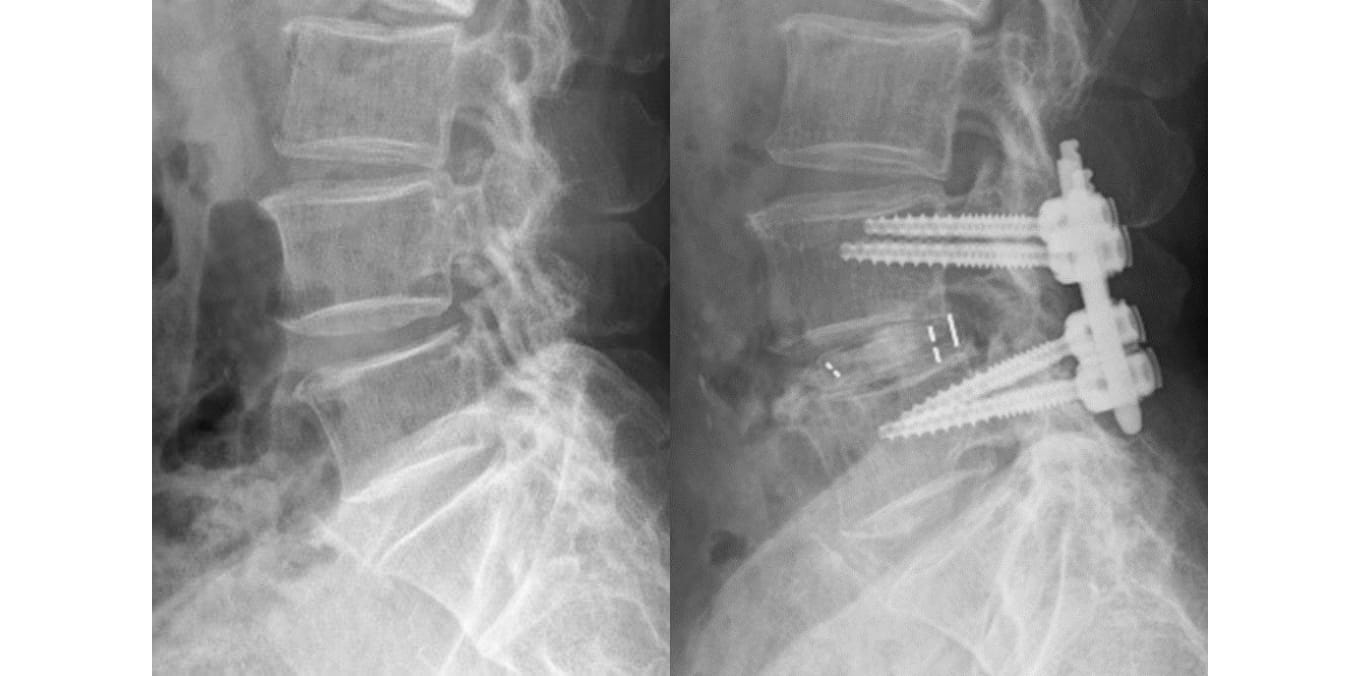

腰椎すべり症(背ぼねが前後にずれる病気)などの、脊椎がグラグラして痛みを生じている場合は、脊椎を安定化させるためにチタン・インプラントによる脊椎固定術が有効です。従来は大きく切開してインプラントを入れる手術が主流でしたが、近年では小切開で手術を行うことが出来るようになりました。椎弓根スクリュー(背ぼねを固定するネジのようなインプラント)を入れる際にも、経皮的スクリュー法(PPS法)や皮質骨経路スクリュー法(CBT法)という方法で、出来るだけ小切開で行うようにしています。

図3-1.MIST法による腰椎固定術の例

図3-2.腰椎すべり症に対する固定術の例 出来るだけ小切開で行うようにしています